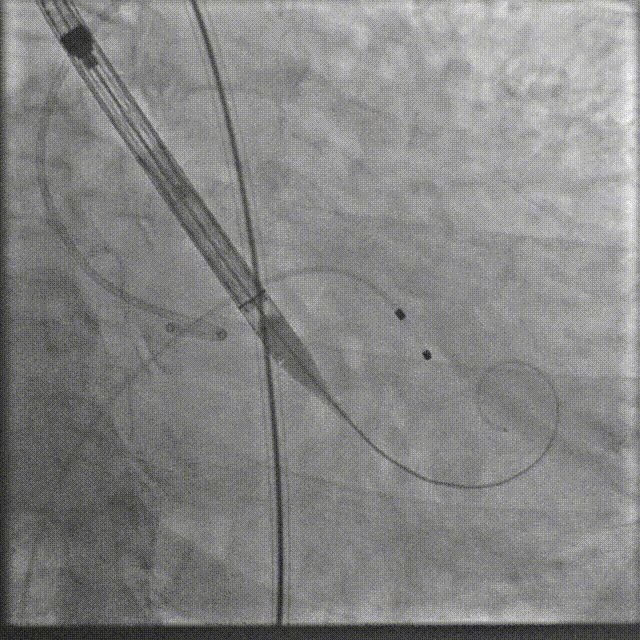

瓣膜系统过弓

定位造影

瓣膜确认位置后释放

回收极限处造影

最终造影

术后复查造影示瓣膜位置满意,形态良好,冠脉显影良好;TTE示轻微瓣周漏;排除入路血管问题,手术圆满成功。